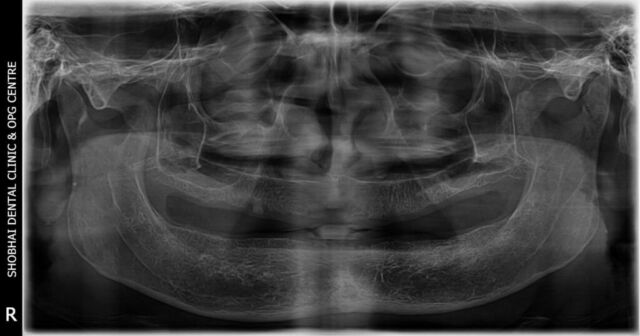

It’s a 500 square feet spacious dental setup located in a prime location in Kalyan west. The Clinic has in house OPG machine for early diagnosis and latest sterilization equipment. Our team is very well trained for handling all types of dental treatments and emergencies.